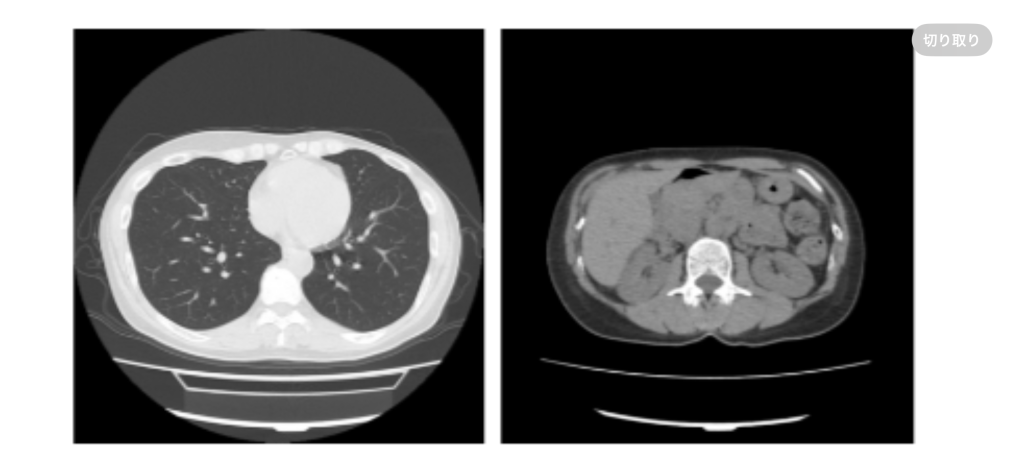

1/15 夜 外ジョギング60分 昨日書くの忘れましたが、先週受けた🍫のCT検査の結果が昨日メールで来ました! 結果は1〜2ヶ月後に‥とのことだったので、あまりの早さにびっくり! マシンの修理もその位、早くてもええよー🤣 気になってたアバラについては、所見はナシ。やっぱり内臓系の検査なのだねぇ。一応内臓系も全て異常無しだったので、良かったです☺️ アバラは良くも悪くもならず、様子見です。

早い結果で異常なし良かったですね。アバラの違和感フェードアウトしてもらいたいですね。 来年度はCT受ける予定でおります。